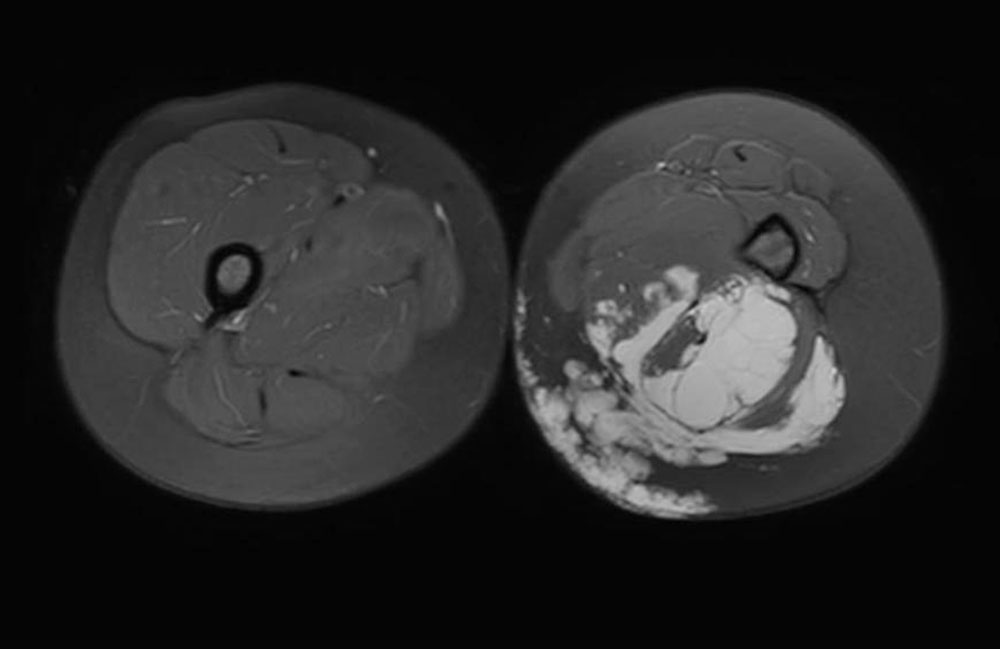

Cross-sectional imaging allows identification of the tissue that accounts for the difference in circumference (fatty tissue? lymphedema?). A subcutis that is thicker and coarser compared to the unaffected side suggests the simultaneous presence of an LM. A narrower muscle layer, on the other hand, indicates an associated partial hypoplasia (immobilization due to pain) and the need for intensive physiotherapy. It is rare for an extensive venous malformation to be intraosseous and even rarer for it to have any clinical significance. However, in view of the considerable variability of the findings, any bone involvement by the venous malformation should be described.

High spatial resolution, good soft tissue contrast, three-dimensional image reproduction and development of specific examination protocols for tissue perfusion and vascular imaging render MRI the gold standard in venous malformation imaging. There is an indication for this if the congenital vascular malformation is extensive and/or painful, i.e., whenever invasive treatment is considered. However, findings of little clinical relevance do not require this type of diagnostic study. In particular, children should not receive unnecessary examinations under anesthesia if invasive therapy is not being considered. In addition to the justifying indication, appropriate know-how in the selection of image sequences is essential for the success of the examination. In a team discussion between clinicians and radiologists, the relevant questions should be clarified, and the appropriate protocol should be chosen. The examination is performed without and with contrast medium as magnetic resonance angiography (MRA), so that the venous malformation can be distinguished from an LM, since the latter does not enhance. A venous malformation is strongly hyperintense (white) in the T2-weighting, especially after fat suppression. In the native T1-weighted images it is hypointense, similar to musculature. After administration of contrast medium it shows slow but almost complete enhancement of the lesion.